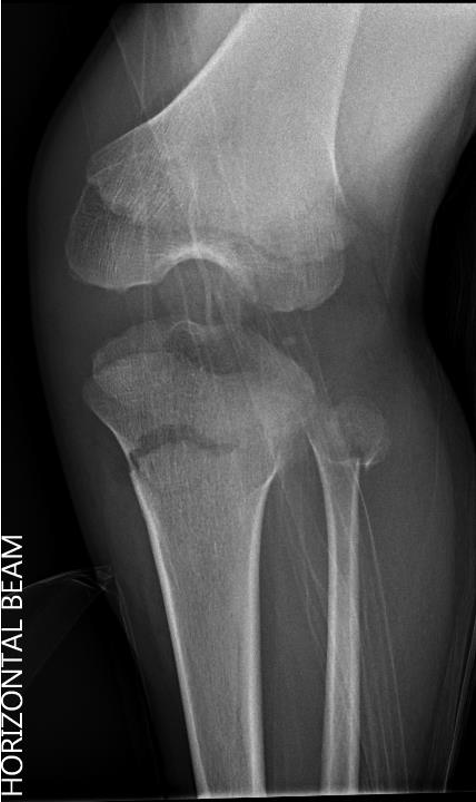

Manipulation and casting of malaligned Cozen fracture under anesthesia

Valgus malalignment